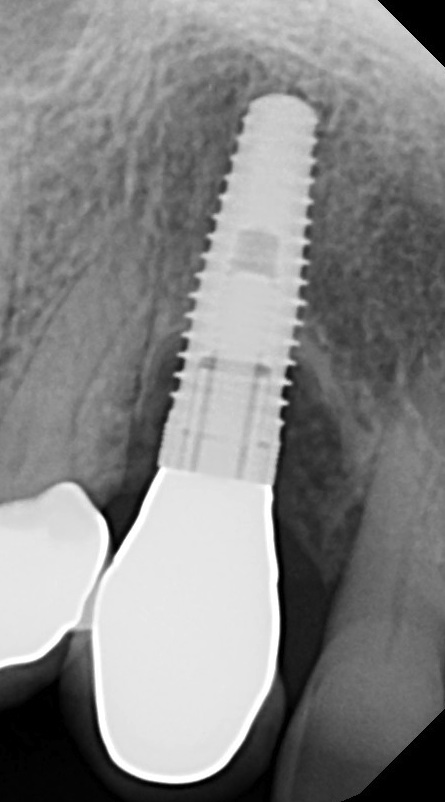

Fig 1. This implant was placed in March 2006. Peri-implantitis was clinically evident in April 2008, with bleeding on probing, suppuration, and increasing probing depth.

Figure 1

With all of the success seen in the dental community relative to implant placement, dentists are now seeing a more pronounced trend in dental implant care: an increase in the bacteriologic and/or traumatogenic occlusion-mediated loss of tissue integrity, accompanied many times by alveolar bone loss. The most common terminology applied to this condition is peri-implantitis (Figure 1). As replete as the dental literature is with success story after success story, there is virtually no detailed and specific prospective clinical trial data on the diagnosis and management of the peri-implant diseases, which result in soft tissue inflammation and the potential for alveolar bone destruction that may lead to the loss of the implant.